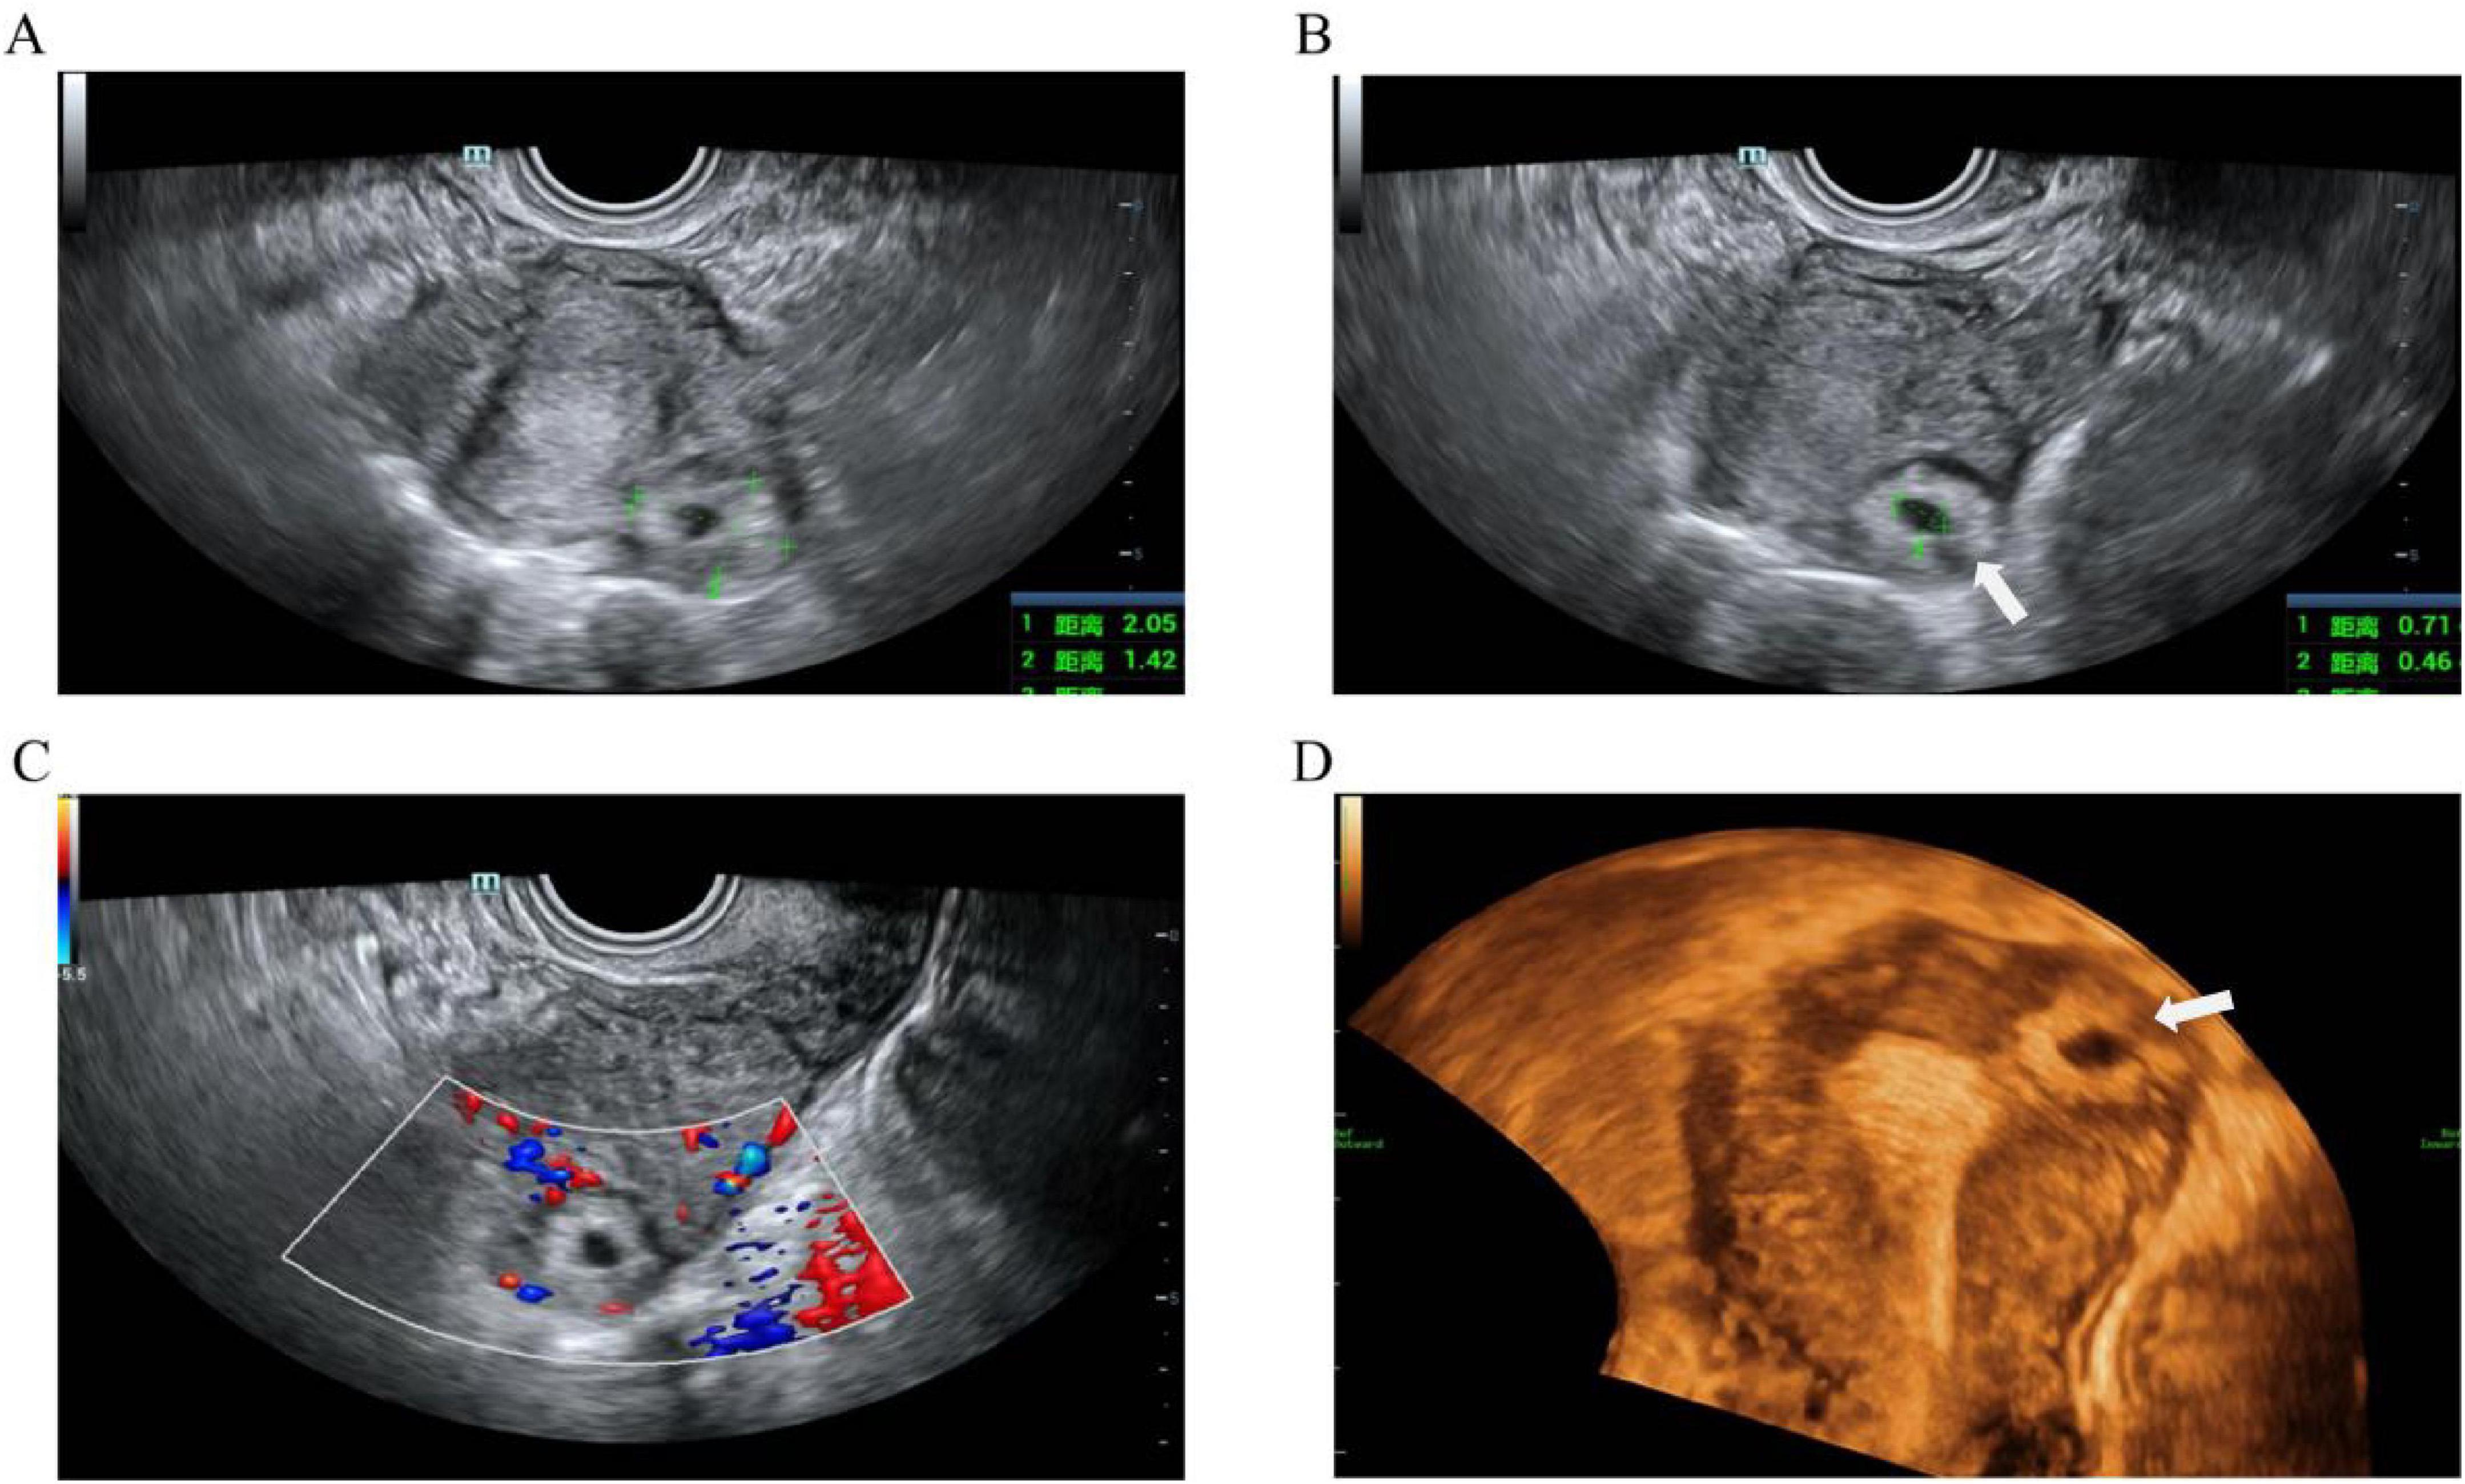

A classification system was proposed by Chinese experts in 2000 (12). Based on the gestational sac’s growth pattern, angular pregnancy is divided into type I and type II (12). The gestational sac of type I angular pregnancy is situated at the mediolateral junction of the uterine cavity, enveloped by two circular decidual bands and partially surrounded by a myometrial layer (Figure 1). The risk of uterine rupture is low, and the pregnancy usually progresses to the mid or late trimester. In contrast, type II angular pregnancy is characterized by the outward growth of the gestational sac toward the cornual region, resulting in significant bulging, associated with an elevated risk of uterine rupture and life-threatening hemorrhage (Figure 2). Utilizing this classification system enables clinicians to enhance their comprehension of diverse pathological processes, thus facilitating the selection of the most appropriate management options to ensure optimal patient prognoses. A diagnosis of angular pregnancy can be made by two-dimensional transvaginal/transabdominal ultrasound (Figure 2) and confirmed with a laparoscopy or laparotomy. The Figure 3 shows a schematic diagram of angular pregnancy.

Figure 2. Type II angular pregnancy: (A) The two-dimensional ultrasound showed a mixed echo pattern mass measuring 21 mm × 14 mm × 18 mm in the left uterine angle, expanding toward the cornual region of the uterus. (B) A mixed echo identified a gestational sac measuring 7 mm × 5 mm × 6 mm. (C) Image of blood flow of AP in the left uterine angle. (D) The 3-dimensional ultrasound showed a mass adjacent to the endometrium, expanding toward the cornual region of the uterus. The arrow indicates a thin myometrial wall.